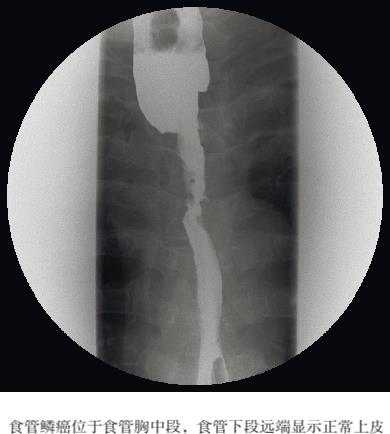

图2.1 双重造影(早期食管癌)

斑块状病变是浸润性生长的早期迹象。为了检测小病灶,必须使用双重对比剂进行多平面检查。黏膜皱襞可能会有轻微增厚,并且可能出现连续性破坏的征象,这种情况下病变中可能残留对比剂。早期食管癌管壁的运动是正常的,往往无法从这一点得到明确诊断的证据(见图2.1)。